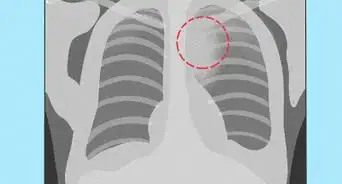

1Know what to expect during a chest X-ray. A chest X-ray is one of the most common X-ray procedures and is used to produce images of the heart, lungs, airways, blood vessels, and the bones of the spine and chest. It's normally used for diagnosing problems such as:[8]

- Shortness of breath, bad or persistent cough, and chest pain or injury.

- It can also be used for diagnosing or monitoring conditions such as pneumonia, heart failure, emphysema, lung cancer, and fluid or air around the lungs.

- If your doctor recommends that you should get a chest X-ray, no special preparation is required – just follow the steps mentioned above.

- A chest X-ray takes about 15 minutes and often requires two views of the chest to be taken.